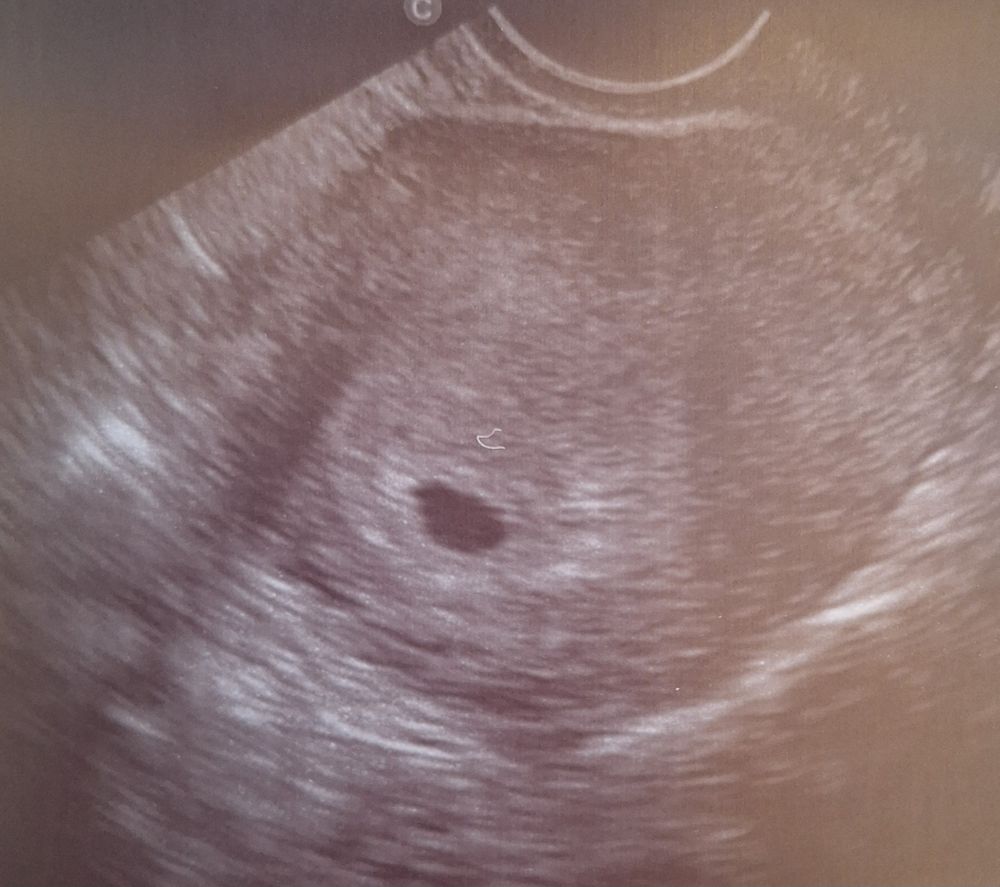

21 дпп узи

Результаты УЗИСегодня было самое короткое в жизни узи, секунд 10, не более 😄

Только зафиксировали, что плодное яйцо в матке, даже не замерили. Врач предупредила, что сейчас смотрим только то, что яйцо в матке.